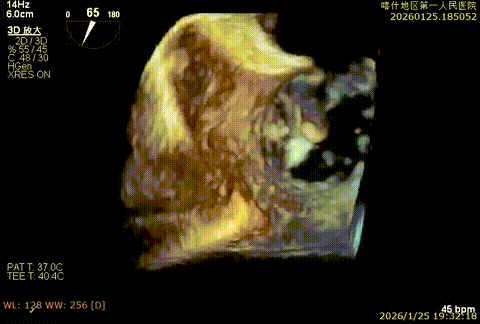

该例患者为DMR,1,2,3区均见脱垂,主要脱垂位于1区及外交界后叶脱垂,病变解剖结构亦相对复杂。术前制定手术策略:使用3把XTR解决患者瓣叶脱垂与二尖瓣反流。术中首先进行房间隔穿刺,最终穿刺高度4.5cm。穿刺成功后将SGC和XTR-CDS依次送入左心房,通过操控“M”旋钮调节SGC,使二尖瓣夹避开华法林脊并成功定位于2区正上方。在2区进行弹道测试成功后,进行Orientation调整。最终在1区将二尖瓣夹送入左心室,成功捕捞和夹持瓣叶后缓慢关紧夹。第二枚XTR植入2区,采用双拉链技术,从两个夹子中间植入第三枚夹子,固定脱垂区域降低反流。TEE检查见二尖瓣反流程度降低至少量,二尖瓣双孔组织桥稳定,肺静脉逆流改善明显,手术安全结束。

3D enface组织桥稳定

3D enface组织桥

3D enface 组织桥稳定

3D enface 反流少量

第三枚双拉链技术XTR从两个夹子中间植入,精准定位,严丝合缝